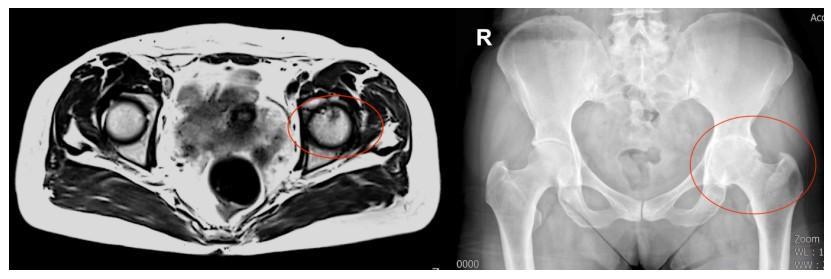

左侧股骨头密度不均匀,左髋关节间隙变窄,关节面密度增高

术后恢复血流的部分股骨头影像